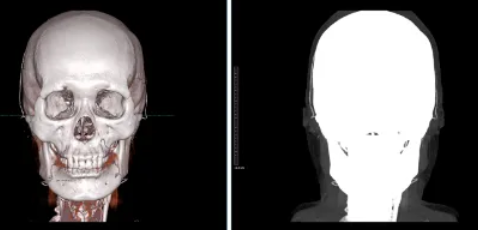

조영제를 넣고 찍은 CT 영상의 volume rendering 결과(좌)와 두개골에 가려진 혈관 구조물(우)

두경부 조영 영상에 있어서 뇌혈관들은 두개골 안에 위치하기 때문에 단순히 조영 영상을 CT로 촬영한다고 직접 확인할 수 있는 것이 아닙니다. 뇌혈관들을 확인하기 위해서는 두개골을 제거하는 과정이 필요하게 되며 이 과정을 bone subtraction이라고 합니다.